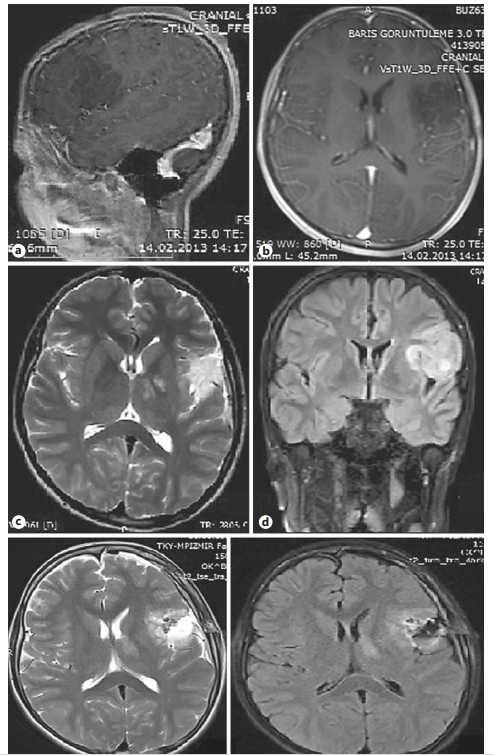

图1。矢状(a)和轴向(b)钆增强MRI显示左侧额叶语言区病变,无增强对比。t2加权(轴向)MR图像(c)显示布洛卡区高信号病变。显示图像(d;冠状)也显示均匀高信号病灶。术后T2(e;轴向)和T1加权MR图像(f;(轴)确认病灶清除。

在局部麻醉和镇静的情况下对患者进行病灶切除和清醒开颅。异丙酚、咪达唑仑和芬太尼的组合用于镇静。异丙酚以2 mg/kg/h持续灌注,咪达唑仑以2或3 mg剂量间隔给药,以保持拉姆齐镇静评分在4或5;开颅前给予芬太尼75μg 1次。手术3 h时咪达唑仑总剂量为24 mg。当需要患者配合时,暂停异丙酚灌注,氟马西尼对抗咪达唑仑(0.4 mg)。病灶切除过程中控制了患者的言语。尽管全部切除了病变,有趣的是没有言语控制障碍。在病灶切除完成后,镇静持续在一个水平足以保持拉姆齐镇静评分在4或5。术中、术后患者言语功能均无明显障碍。术后早期头颅MRI证实病灶全部切除(图1 e,f)。患者术后一周出现局灶性癫痫发作,表现为失语症。组织病理学报告病变为胚胎发育异常神经上皮肿瘤。在24个月的随访期间,患者接受抗癫痫治疗,并保持无癫痫发作。他的学校和社交生活质量都有了的提升。